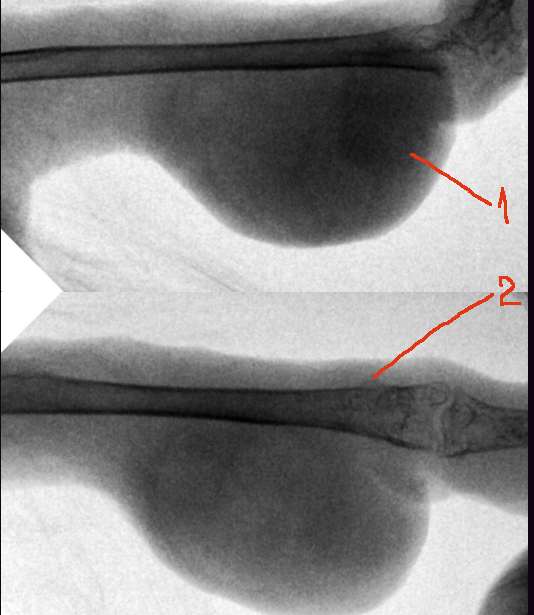

Zosia Опубликовано 30 января, 2020 #16 Опубликовано 30 января, 2020 Кость целая,без патологических изменений, без зон распада или абсцессов Броди. Возможно есть какие-то проблемы в суставе (кажется низковатой плотность, возможно след старой травмы СУСТАВА). Я сделала инверсию снимка, видится некое образование,кистоподобное, на латеральной проекции. Возможно исходит из суставной сумки (цифра 1). Это м.б. абсцессом, гигромой- но связано скорее всего с соедигнительной тканью. На склеродермию или подагрическое образование непохоже. На ВД проекции в нижней четверти кости есть (возможно это артефакт) некое нарушение четкой границы кости (цифра 2)... но параметры снимка не позволяют с уверенностью эту неровность оценить. Вопросы: Есть ли проблемы с дыханием Есть ли проблемы с пищеварением (рвота напрмиер) И нужен рентген "всей птицы", хотя бы один...

Dukemc Опубликовано 31 января, 2020 Автор #26 Опубликовано 31 января, 2020 23 часа назад, Zosia сказал: Кость целая,без патологических изменений, без зон распада или абсцессов Броди. Возможно есть какие-то проблемы в суставе (кажется низковатой плотность, возможно след старой травмы СУСТАВА). Я сделала инверсию снимка, видится некое образование,кистоподобное, на латеральной проекции. Возможно исходит из суставной сумки (цифра 1). Это м.б. абсцессом, гигромой- но связано скорее всего с соедигнительной тканью. На склеродермию или подагрическое образование непохоже. На ВД проекции в нижней четверти кости есть (возможно это артефакт) некое нарушение четкой границы кости (цифра 2)... но параметры снимка не позволяют с уверенностью эту неровность оценить. Вопросы: Есть ли проблемы с дыханием Есть ли проблемы с пищеварением (рвота напрмиер) И нужен рентген "всей птицы", хотя бы один...

Zosia Опубликовано 1 февраля, 2020 #27 Опубликовано 1 февраля, 2020 На второй лапе- зона артроза или подагрических отложений (четкости никакой).